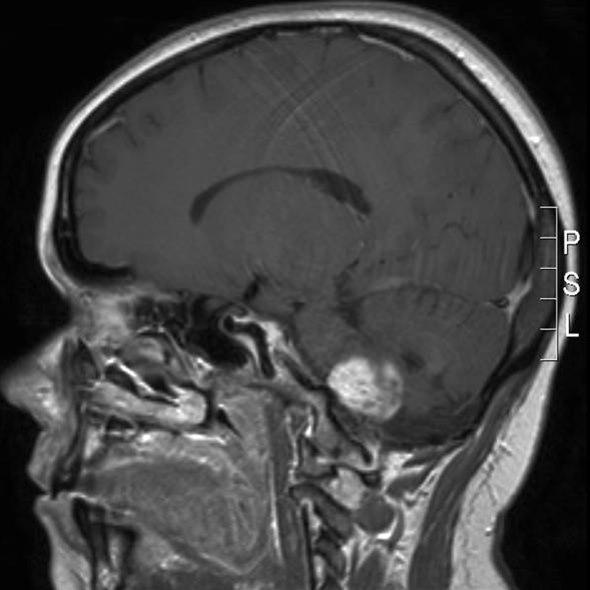

Pilocytisk astrocytom, sagittalt snitt

Pilocytisk astrocytom WHO grad I

Gjengitt med tillatelse av Radiologisk avdeling, Universitetssykehuset Nord-Norge